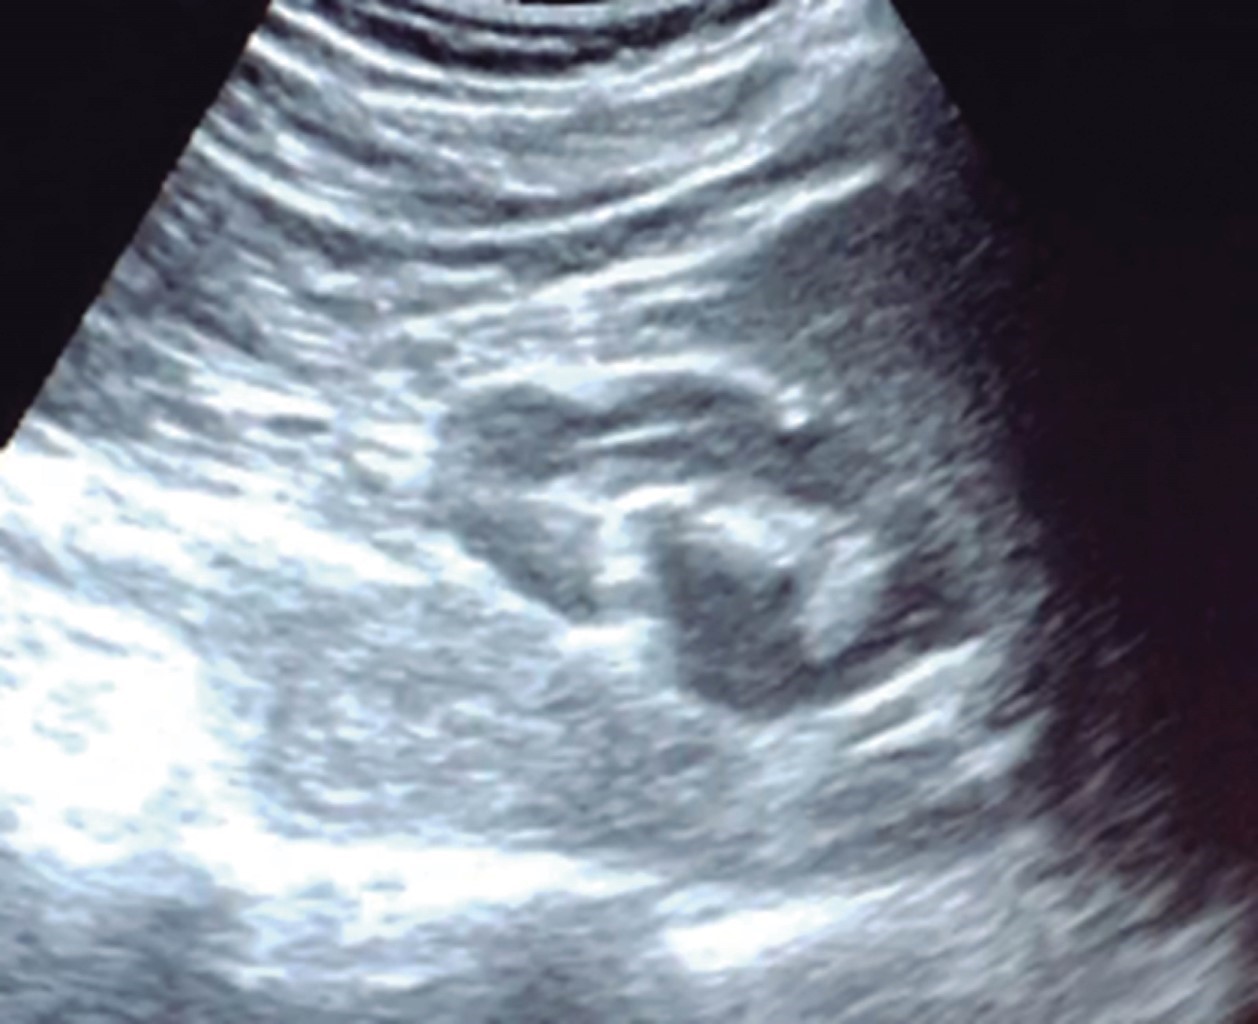

The general surgeon deals with clinical problems involving the digestive tract, the neck, the abdominal wall, and disorders of the circulatory system and the thorax. A paper published in 2008 by Lindelius,15 demonstrated that the implementation of ultrasound by the general surgeon in cases of acute abdominal pain increased diagnostic accuracy by 7.9%. In the daily consultation of the specialty, incorporating sonographic scanning to the explored area adds minutes to the clinical examination that provides data of notable value due to its objectivity and precision. The abdomen is usually the site most frequently explored by general surgeons. It is possible in a daily consultation to do the entire upper abdominal ultrasound protocol in minutes, which includes both upper quadrants and the flanks, being able to observe the liver, gallbladder and bile ducts, both kidneys, the spleen, part of the pancreas and, with the help of color Doppler, the main vessels of the region such as the inferior vena cava, abdominal aorta, portal vein, splenic vessels, and the hepatic artery. There may be limiting factors such as gastric contents, the filling level of the gallbladder, or the patient's constitution and ability to cooperate with the study. However, with daily practice, sufficient skills and refinement are acquired to achieve, with accumulated experience, images of immediate diagnostic relevance. In the training phase, contrasting our findings with information available on the web, with imaging colleagues, or surgeons already experienced in ultrasound, will allow the essential feedback and mentoring of any learning curve. Traditionally, it was considered that those organs containing a mixture of liquid and gas (intestine, stomach) are not assessable by ultrasound; the gas produces a rarefaction effect, as it does not compress the waves as a solid tissue or a liquid medium, the signals are then scattered preventing them from returning as echoes and allowing the processor to form an image congruent with the scanned organ. However, when this condition changes due to a pathological state, it is possible to identify the intestinal or gastric contents and give us a more approximate idea of what is happening in that abdomen. We can, for example, tell whether a stomach is full of liquid or whether the intestine contains solid, liquid, or gaseous residue. Today's equipment can even see the intestinal wall in detail when it is dilated. It can be distinguished when the colon is fluid-occupied at the level of the left flank as might be in amebic colitis or intestinal occlusion,16 where dilatation of the small bowel ≥ 25 mm, abnormal peristalsis, the presence of free intraperitoneal fluid and edema of the bowel wall are seen (Figure 2). In cases of acute abdominal pain, ultrasound can immediately allow differential diagnoses, such as the finding of a pyelocaliceal dilatation due to nephrolithiasis (Figure 3) or an abdominal aortic aneurysm (Figure 4). A prospective study performed in Irvine, California,17 found that the diagnostic ability of the first contact physician performing ultrasound to detect cholelithiasis has a specificity of 87% and a sensitivity of 82%, while the ultrasonography test performed by an imaging physician had a sensitivity of 83% and a specificity of 86%. In other words, by saving the patient's time, the diagnosis of cholelithiasis is feasible by adding a few minutes to the initial physical examination. In cases of appendicitis, the diagnostic method considered the gold standard is computed tomography (CT). However, it has drawbacks, such as its availability, its cost, and the risk of radiation in children and pregnant patients. In such situations, especially in children, females, or thin patients, ultrasound is a powerful tool that complements the initial clinical examination. The advantages of ultrasound over CT are its ubiquity (it is already in the emergency room), low cost, absence of radiation, and differential diagnosis with gynecologic or genitourinary causes of pain. In appendicitis, the sensitivity and specificity of CT are 99.4% and 80.0%, respectively. For ultrasound, the diagnostic sensitivity is 83% and specificity is 90%. The rate of negative appendectomy is slightly higher in the CT group than in the ultrasound group, i.e., 7.1% (3/42) (CT) compared to 4.67% (5/107) (ultrasound). It should be emphasized that ultrasound is an operator-dependent technique. Experience and quality of the equipment play an important role.18 Appendicitis has several characteristic findings, such as an edematous wall and general thickening. A noncompressible non-peristaltic tubular structure measuring more than 6 mm in diameter in the right lower quadrant is taken for criteria of positivity (Figure 5).19-21